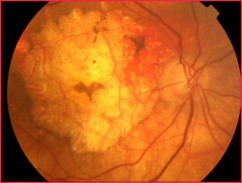

Imagerie et diagnostic différentiel de l’atrophie géographique

Introduction à la DMLA sèche et à l’atrophie géographique (maculaire)